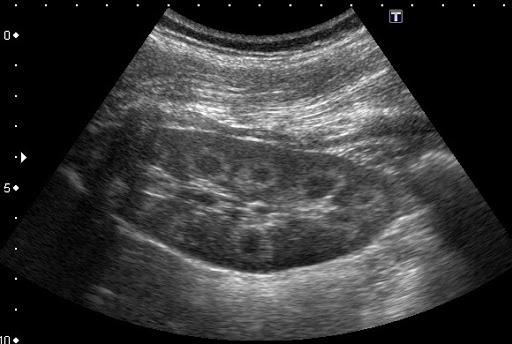

ПАП-тест является процедурой, которая позволяет выявить серьезные проблемы со здоровьем на ранних этапах, когда заболевание еще поддается лечению. Цитологический скрининг или ПАП-тест – рекомендуется проходить каждой женщине, достигшей 21 года и начавшей жить половой жизнью, с интервалом раз с три года. При наличии в анамнезе факторов риска врачи настоятельно рекомендуют проходить обследование чаще, хотя бы раз в год.